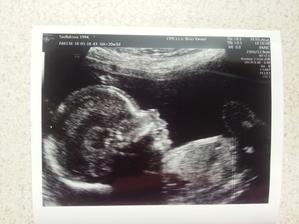

16.3. Druhý screening - všechno v naprostém pořádku 🙂 potvrzená znovu holčička :-*.